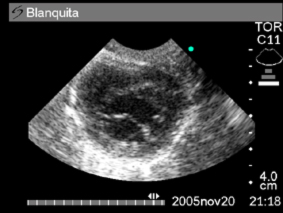

El informe radiográfico de»Blanquita» concluye neumonía intersticial y cardiomegalia de predominio izquierdo (foto Nº 2 y 3) También se le había realizado previamente una ecografía abdominal concluyendo nefropatía glomerular infiltrativa bilateral.

En la ecografía abdominal se reitera la nefropatía bilateral con la existencia de relación cortico-medular disminuída. Como hallazgo se detecta liquido sanguinolento libre en abdomen. Se punciona la cavidad abdominal extrayendo 11 ml de liquido sanguinolento denso y celular. Al frotis se observan glóbulos rojos en su mayoría.